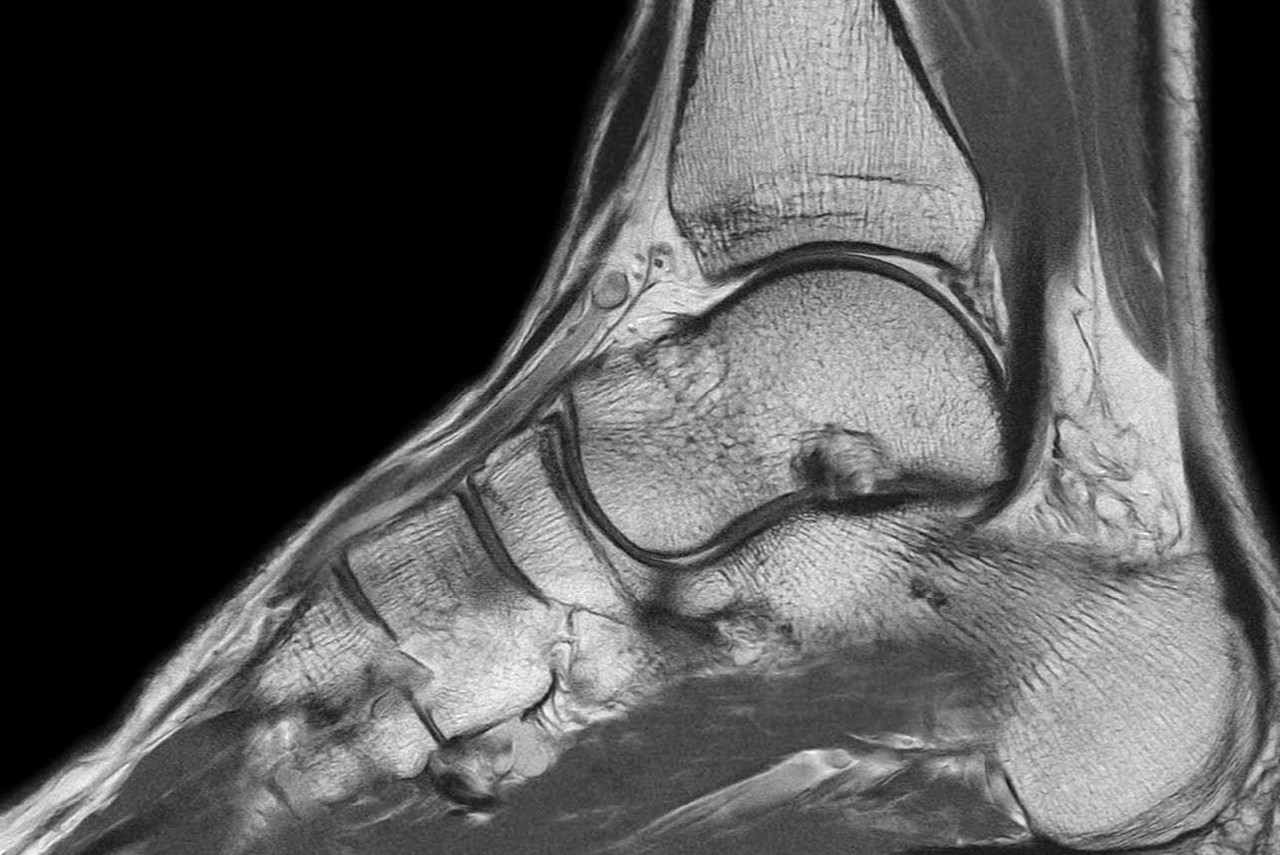

Sports imaging plays a key role in identifying and treating injuries caused by exercise or sports. It is used to evaluate a wide range of conditions, such as fractures, ligament and tendon tears, muscle strains, and inflammation of joints or tissues. Common areas include the knee, foot and ankle, shoulder, elbow, wrist, hips, groin, and hamstrings.

Sports injuries are typically categorised as either overuse injuries or traumatic injuries. Overuse injuries develop from repetitive movements or strain and include conditions like tendinosis, arthritis, and stress fractures. Traumatic injuries occur due to sudden impacts or accidents and can involve dislocations or bone fractures.